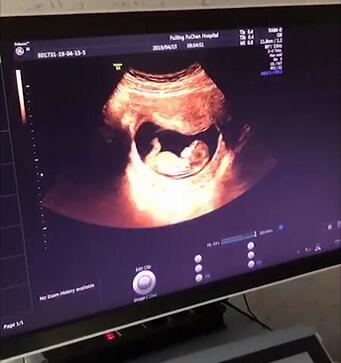

产检NT、唐筛、四维彩超、糖耐量试验,你都做了吗

产检NT、唐筛、四维彩超、糖耐量试验,你都做了吗?